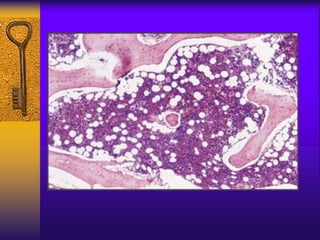

BM Aspiration BM Biopsy

BM biopsy

hypocellular ,increased fat spaces

Bone Marrow:

– Hypocellular:

<50% of normal cellularity Trephine biopsy is

the most important for diagnosis.

– Most of the cells present are lymphocytes,

plasma cells.

– Iron stores: increased